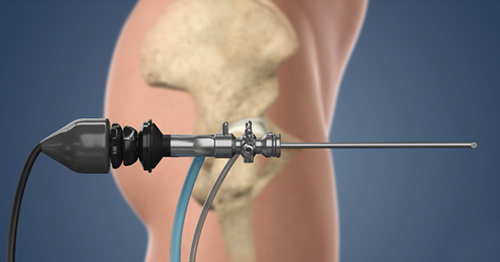

- Hip Arthroscopy: This minimally invasive procedure allows surgeons to access the hip joint to remove bone spurs, repair damaged cartilage, and address any structural abnormalities contributing to FAI.